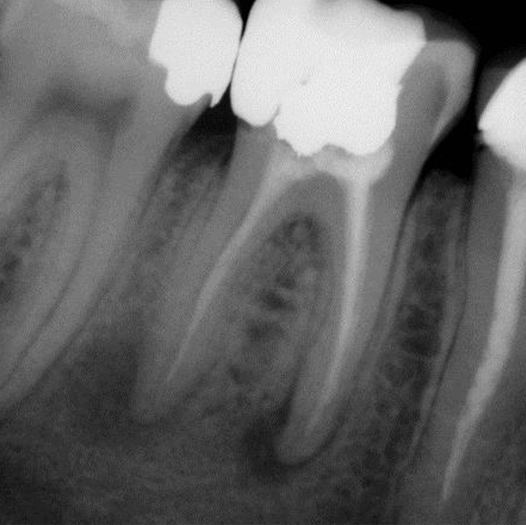

Before

Before Root Canal treatment